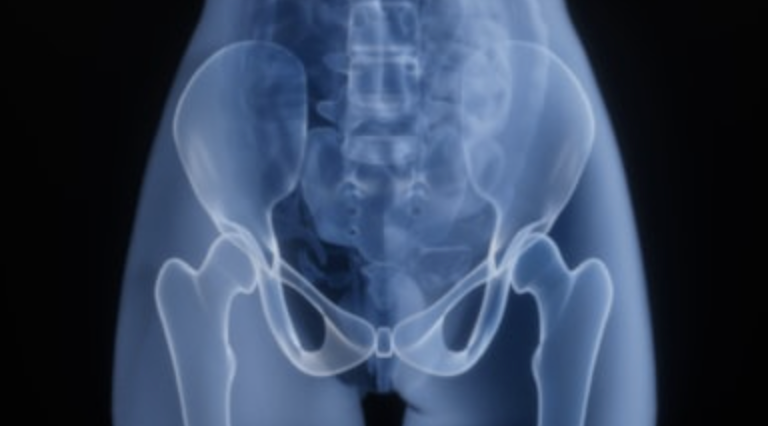

股関節の痛みの原因?|先天性股関節脱臼(臼蓋形成不全)とは

「歩くと股関節が痛い」「昔から股関節が硬い気がする」「女性で変形性股関節症と言われた」 このような股関節の痛みの背景に多いのが、👉 先天性股関節脱臼(現在では発育性股関節形成不全)や臼蓋形成不全です。 特に日本人女性に多 […]